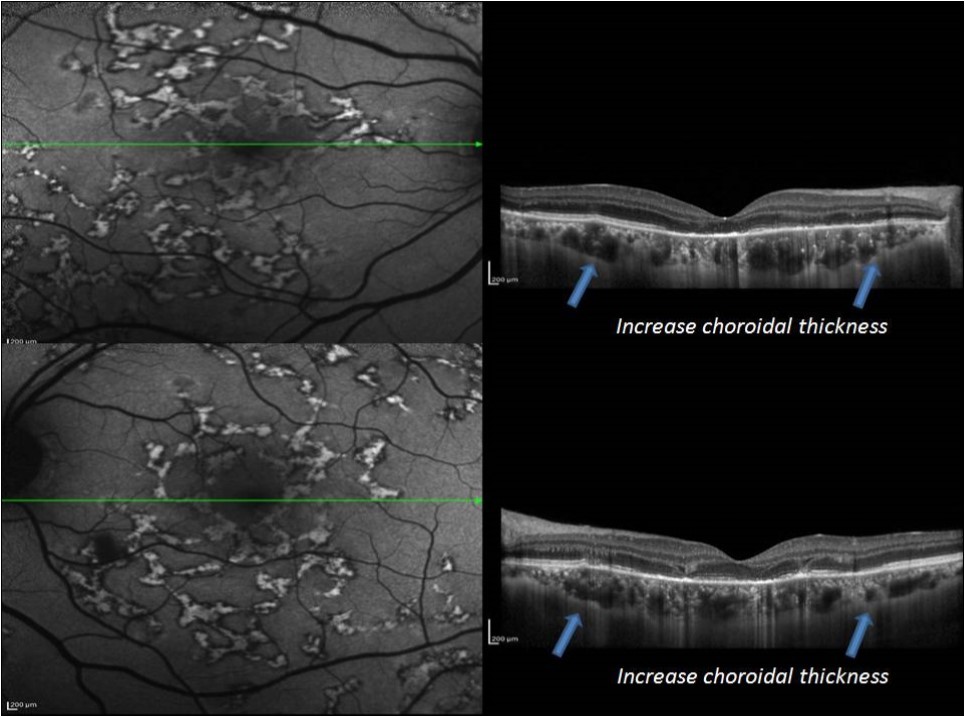

Figure 6.EDI-OCT in acute stage of MSC reveled increase choroidal thickness

In acute stage, SD-OCT showed hyperreflective areas involving the outer retinal layers which include retinal pigment epithelium (RPE), photoreceptor outer segment tips (POST), inner segment–outer segment (IS/OS) junction, external limiting membrane (ELM), and outer nuclear layer (ONL) with choroidal and intraretinal layer cells infiltrate. EDI-OCT showed increase choroidal thickness.

In an attempt to explore the extent of choroidal involvement during various phases of MSC, we prospectively studied the EDI-OCT changes in eyes with tubercular MSC.

1. In an acute lesion of MCS, there was an ill-defined area of increased autofluorescence around the lesion. The SD-OCT passing through the area showed a localized, fuzzy area of hyperreflectivity in the outer retinal layers involving the RPE, photoreceptor outer segment tips (POST), photoreceptor inner segment–outer segment (IS/OS) junction, external limiting membrane (ELM), and the outer nuclear layer (ONL). The lesion was localized external to the outer plexiform layer with a mild distortion of the inner retinal layers. Choroidal and intra retinal layer cells infiltrate with corresponding increase thickness of choroid and inner retinal layers more obvious in EDI-OCT. There was no increased backscattering from the inner choroid.

Also our EDI-OCT observation demonstrated a diffuse choroidal thickening as well as localized changes in the deeper choroid beneath the active as well as healed lesions. This could suggest a choroidal involvement deeper to choriocapillaris. we believe that a diffuse increase in choroidal thickness may indicate an immunological trigger. The predominant and an early involvement of RPE may indicate the infective trigger which is go with Yeh et al who have hypothesized that RPE may be the site of primary insult and hence, more severely damaged in presumed tuberculosis-associated serpiginous-like choroidopathy based on the report of the isolation of mycobacterial DNA from RPE cells .11

Takahashi and associates used (EDI-OCT) to evaluate a 40-year-old woman with active, peripapillary SC with testing for known infectious causes of MSC was unrevealing in their study. They found that Prior to treatment subfoveal choroid was found to be markedly thickened (average713.3 ± 4.5 microns) and EDI-OCT localized the active peripapillary placoid lesions to just beneath the RPE, supporting published pathological studies showing diffuse choroidal inflammation with primary involvement of the choriocapillaris in areas of active placoid lesions in eyes with SC. Following treatment, subfoveal thickening decreased dramatically to 330 microns. This finding support the cilinical evidence that choroidal involvement is primary and the predominat insult in SC.12,13